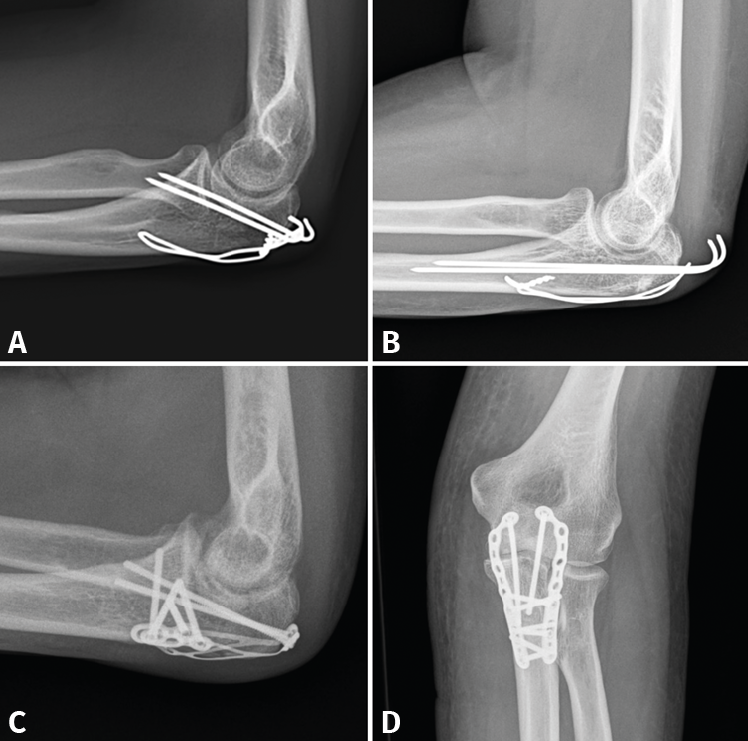

- 2A/2B: son las más frecuentes. La técnica de elección en las fracturas simples en 2 partes es un cerclaje de alambre (obenque) sobre 2 agujas de Kirschner (AK) ancladas a la cortical anterior o colocadas intramedulares. En el primer caso, tenemos riesgo de lesionar las estructuras neurovasculares volares, por lo que no deben sobresalir más de 10 mm; en el segundo caso, el riesgo de que migren proximalmente es mayor(34,35). Se pensó que con este montaje las fuerzas de tensión se transforman en fuerzas de compresión, pero varios estudios realizados no han podido demostrar este principio(36). En las conminutas 2B se recomienda fijación con placa, precisamente para evitar la excesiva comprensión de la cavidad sigmoidea que llevaría a una artrosis precoz. Se recomiendan las placas premoldeadas LCP (locking compression plate). Su efectividad y seguridad están de sobra probadas; sin embargo, al ir en una posición dorsal y ser el cúbito subcutáneo, pueden producir irritación de los tejidos blandos y con cierta frecuencia hay que retirarlas. Aun así, el índice de retirada es mucho mayor en los cerclajes, que puede llegar hasta el 90%(37,38). La alternativa es usar 2 placas laterales de bajo perfil colocadas a ambos lados de la cresta, una medial y otra lateral, que además tienen la ventaja de permitir una fijación bicortical de los fragmentos más proximales. En cualquier caso, los estudios demuestran que ambos métodos tienen buenos resultados y no existen diferencias a corto plazo. Últimamente, se están publicando modificaciones a la técnica clásica del obenque, usando una sutura trenzada de alta resistencia en lugar de alambre(39). En este caso solo tendríamos que retirar las AK y este es un proceso mucho menos invasivo (Figura 8).

- 3A, IB, 2B, 3B: siempre que exista conminución o inestabilidad, el tratamiento de elección será la osteosíntesis con una placa de ángulo fijo LCP, con tornillos de bloqueo adaptados anatómicamente que permiten reducir casi todos los fragmentos.

Figura 8. Ejemplos de fracturas de olécranon en 2 partes (tipo 2A) fijadas con obenque (A y B) y fracturas de tipo 2B fijadas con distintos diseños de placas (C y D).